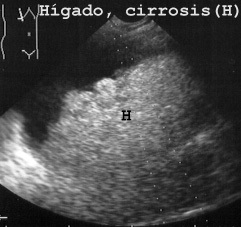

El hígado en la ecopsia (Fig 4)

04HIGDOS.JPG (36534 bytes)

Fig 4

a diferencia de lo que ocurre en la vida muestra ecoestructura hiperecóica (trazos brillantes y blanquecinos en la imagen). Esto es debido a la falta de flujo sanguíneo. Además las venas hepáticas no se ven en el cadáver a diferencia que en el vivo que son muy evidentes como espacios anecoicos o hipoecóicos (oscuros o negros) (FIG 5).

La patología en el hígado fue fácil de demostrar. Como ejemplos presentamos las figuras 15, 16 y 17 de cirrosis, cirrosis con hepatocarcinoma y de metástasis tumoral.

15CIRROS.JPG (21095 bytes)

Fig 15